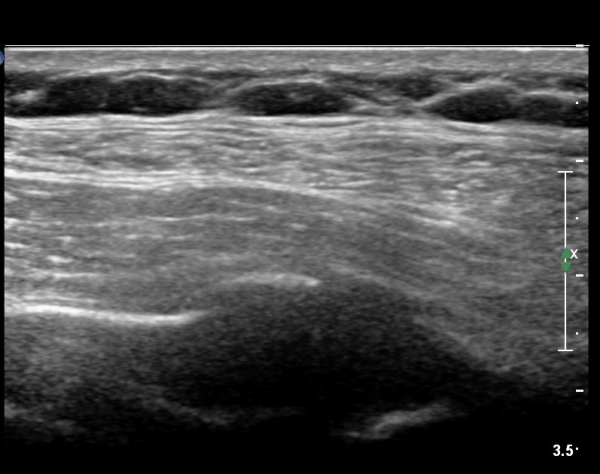

on moving of prove a little, there is bony protrusion(osteoblastic lesion) and hypoechoic(osteolytic)  lesion(image 2, 3, 4).

in transverse scan, visualization of osteoblastic mass with central osteolytic lesion(image 5, 6).

As like this case, visualization of osteoblastic lesion and osteolytic lesion in simultaneously  suggests a malignant mass.